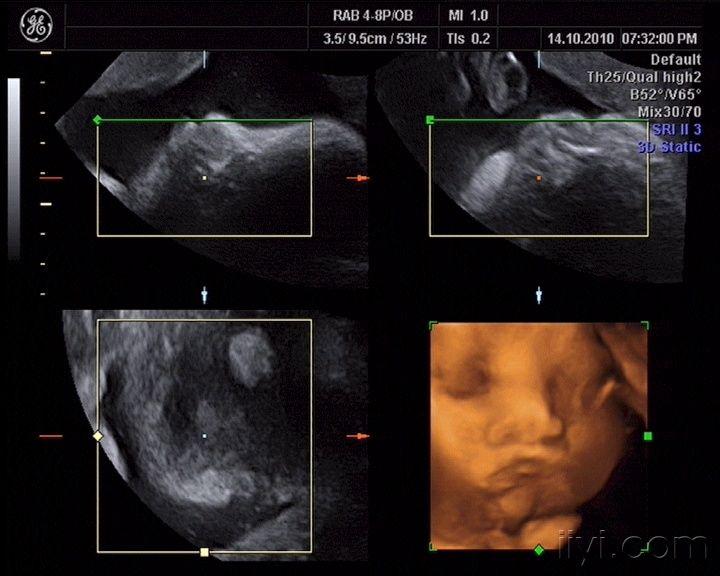

胎儿颅内结构超声切面

胎儿颅内结构超声切面,胎儿脑部超声切面图解

胎儿超声标准切面详解

【新手必看】中孕期胎儿超声检查 — 颅脑和颜面部分

胎儿脑部超声切面图解

胎儿头颅超声解剖图谱

胎儿双顶径切面图解

胎儿丘脑水平切面图解

丘脑水平横切面超声图

胎儿丘脑平面图解